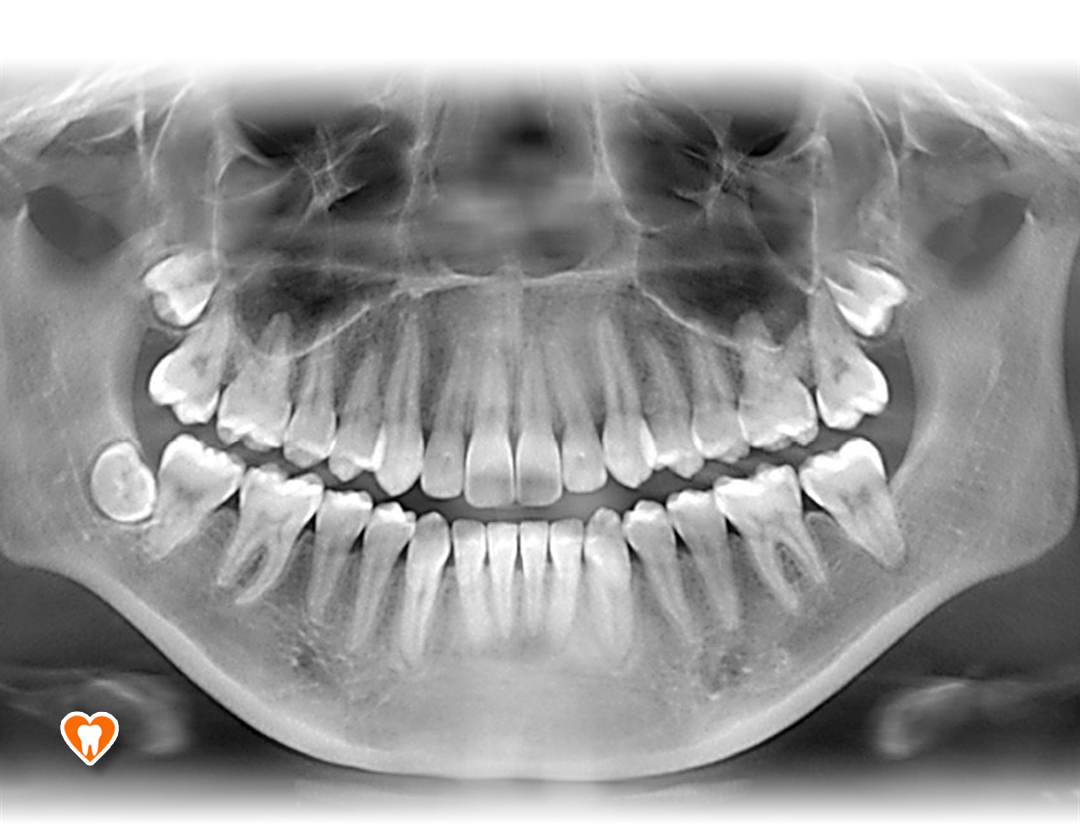

Zdjęcia radiologiczne:

• Pantomograficzne:

Jest to zdjęcie przeglądowe przedstawiające ogólny stan wszystkich zębów, zawiązków zębów oraz struktur je otaczających takich jak kości szczęki i żuchwy, stawy skroniowo-żuchwowe i częściowo zatoki szczękowe,

W naszym gabinecie, dzięki zastosowaniu najnowszych urządzeń do radiowizjografii firmy Carestream, dostosowujemy indywidualnie do każdego pacjenta dawkę promieniowania, niezbędną do wykonania zdjęcia, jednocześnie minimalizując ją, aby każdy pacjent był bezpieczny.